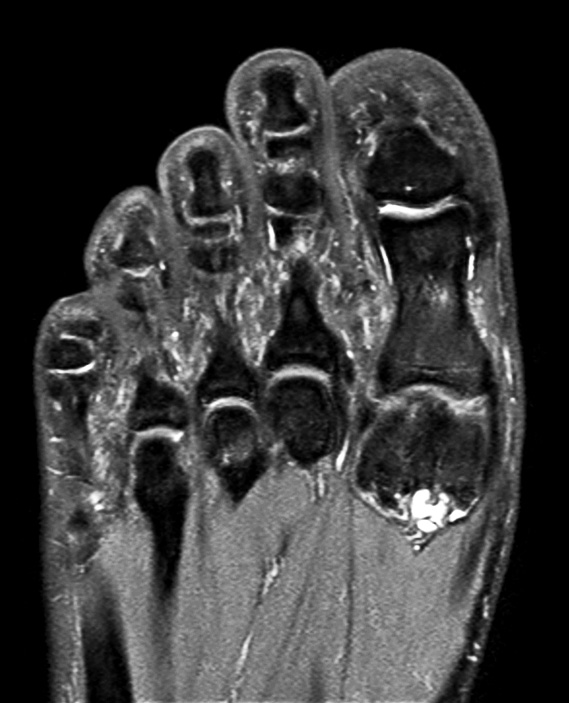

Sagittal PDw mDIXON TSE  (water only)